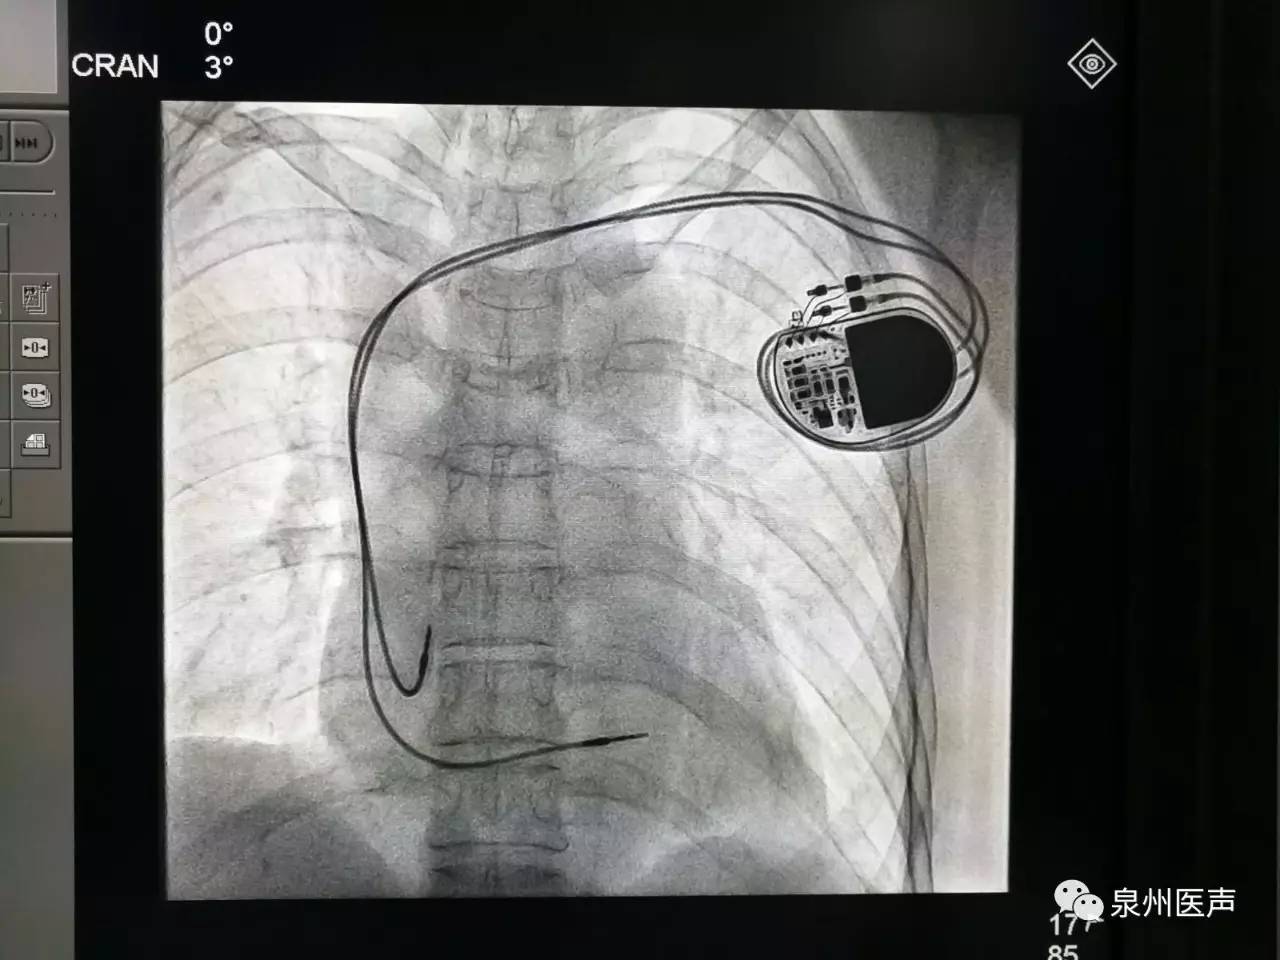

微創(chuàng)、樂普、先健填補(bǔ)國(guó)產(chǎn)起搏器市場(chǎng)空白,釋放哪些信號(hào)?